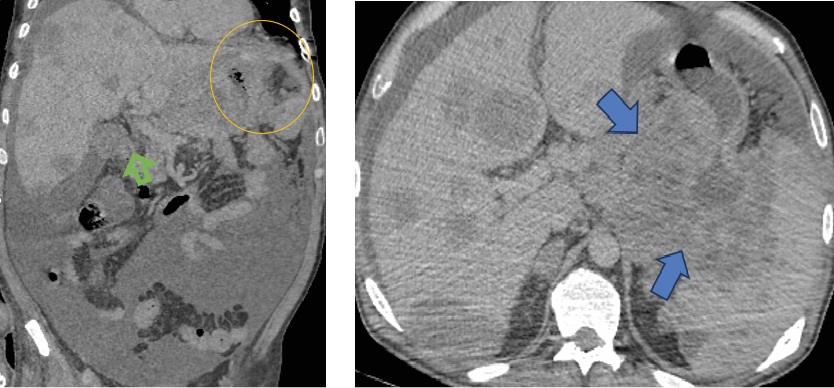

Для оценки динамики лимфомы проведено повторное комплексное компьютерно-томографическое исследование (рис. 2).

а б

Рис. 2. Компьютерная томография органов брюшной полости: а – коронарная проекция; б – аксиальная проекция.

В динамике увеличение в размерах образования желудка (желтый круг) и распространение в поджелудочную железу и селезенку (синяя стрелка); увеличение в размерах и количестве очагов печени (зеленая стрелка). Асцит

Примечание: изображение авторов.